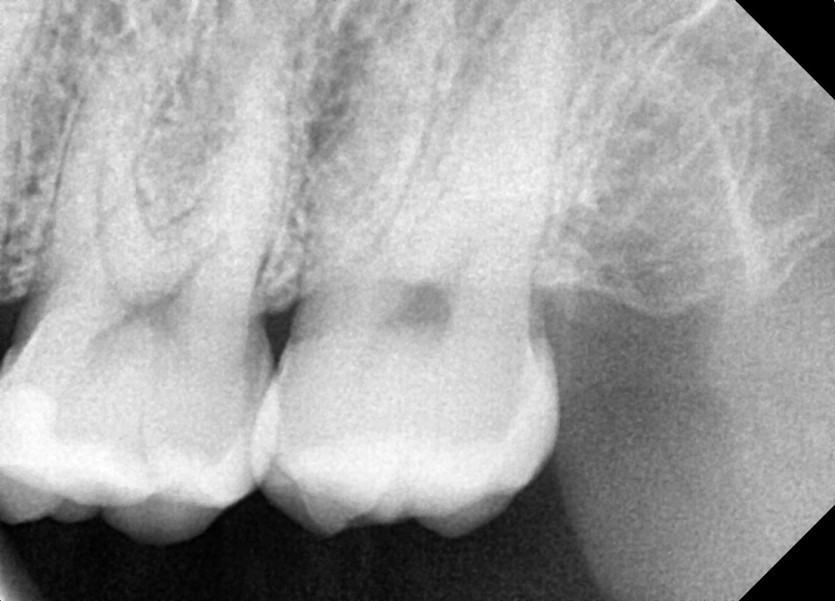

#28,38 사랑니 발치

구강 외과 전문의가 당일 발치했습니다.